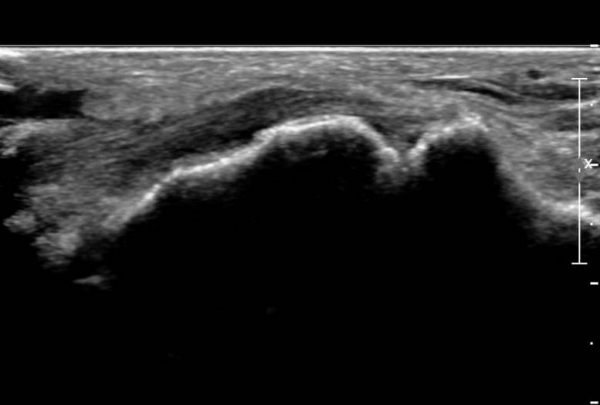

ÃÊÀ½ÆÄ ¼Ò°ß :  Àü°æ°ñ°Ç Á¾´Ü¸é°Ë»ç¿¡¼­ Àü°æ°ñ°ÇÀÌ °í¿¡ÄÚ¼¶À¯È­(hyperechoic fibrillar pattern) ¾ç»óÀ¸·Î °üÂûµÇ´Âµ¥

¼³Çü°ñ ºÎÂûºÎ¿¡¼­ °æ¹ÌÇÑ Á¦¿¡ÄÚ ¾ç»óÀÌ °üÂûµÈ´Ù(»çÁø 1, 2).